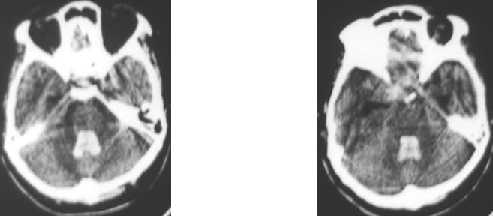

Nontraumatic ICH : intraventricular hemorrhage